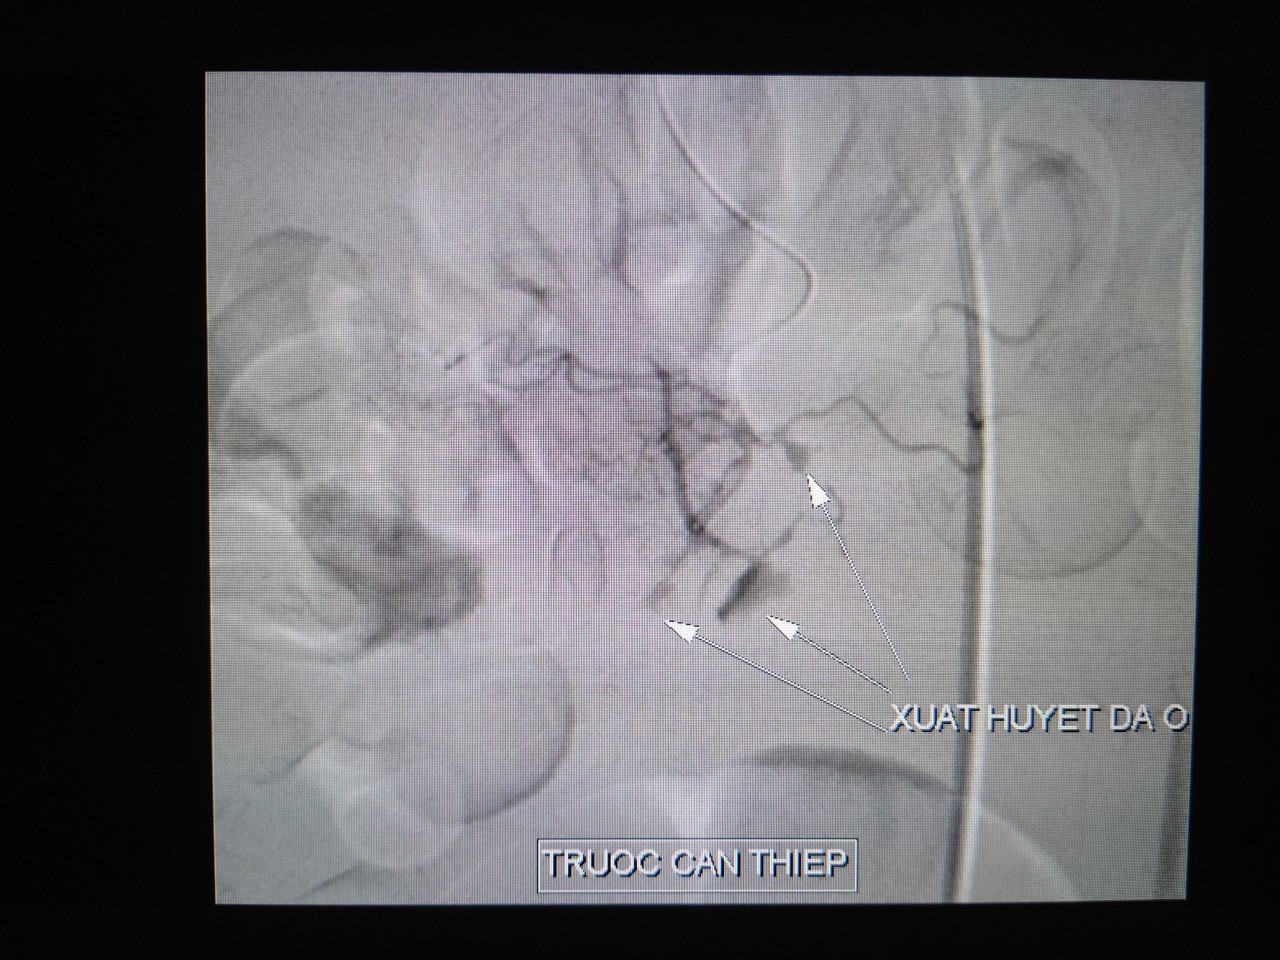

| Hình ảnh xuất huyết đa ổn do vỡ phình động mạch vị tá - Trước can thiệp. (Ảnh: Bv cung cấp). |

Bệnh nhân được siêu âm bụng kiểm tra, phát hiện nhiều máu đông trong ổ bụng, máu tụ sau phúc mạc. Bệnh nhân sau đó được chỉ định chụp và can thiệp nội mạch với chẩn đoán xuất huyết nội do vỡ phình động mạch vị tá tràng. Ê-kíp bác sĩ tiến hành tắc mạch bằng hỗn hợp keo. Sau 40 phút can thiệp, tình trạng huyết động bệnh nhân ổn định. Hiện bệnh nhân tỉnh, sinh tồn ổn, niêm hồng, bụng mềm, không sốt, đang được theo dõi và tiếp tục điều trị tại Khoa Ngoại lồng ngực - Mạch máu bệnh viện.